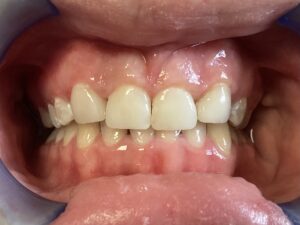

This patient arrived at my practice last week with 2 congenitally missing laterals incisors. Her orthodontist moved the canines into the position of the lateral incisors to fill the gaps but canines don’t look like incisors. They are pointy and “fat” so I told them upfront that although perfect aesthetics will not be achieved we can greatly improve the look and also remove the decay. The procedure required a single 2hr appointment and a very pleasing result was achieved with a very happy teenager leaving the practice that day. Further improvements can be done at a next visit by removing the white spots on the first premolars.